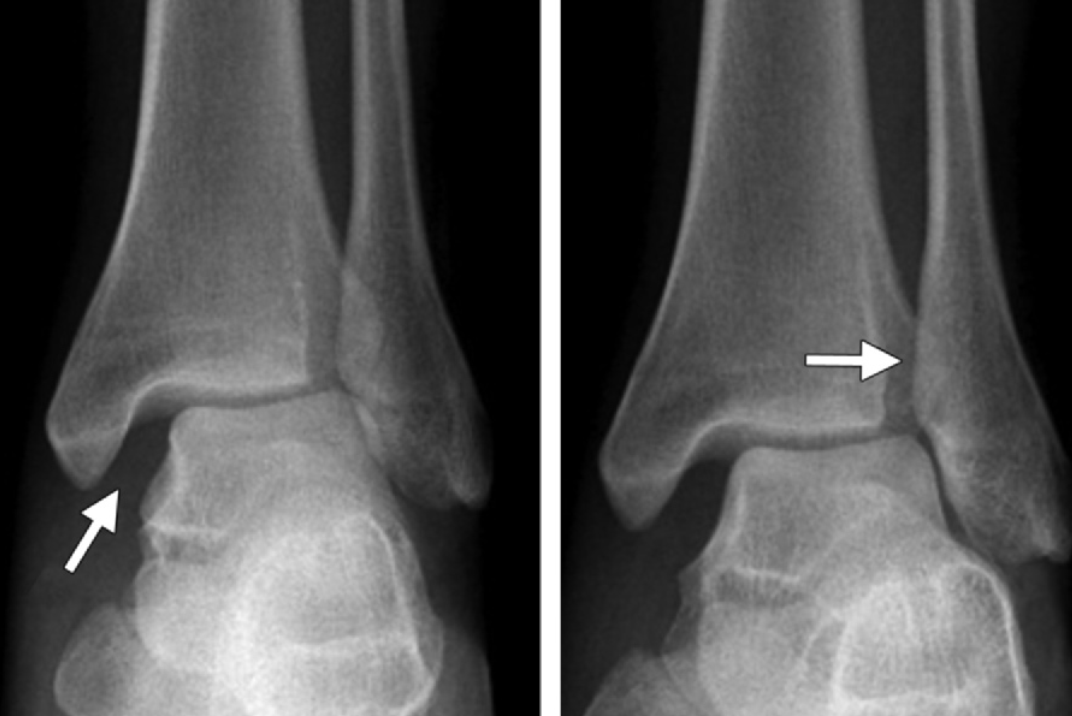

X线摄片是初步评估远端胫腓联合损伤的首选影像学检查方法,对判断骨折、识别胫骨与腓骨远端解剖关系异常具有重要作用。负重位踝关节X线片(包括正位、侧位和踝穴位,踝穴位为小腿内旋15°~20° 的正位片)是检出胫腓联合异常的关键。此外,对可疑病例,需拍摄胫骨和腓骨全长的正侧位 X 线片,以评估近端骨折情况 。

无论是否合并骨折,踝关节扭伤时均可能发生胫腓联合损伤,不能仅凭骨折分型排除该损伤。不同骨折类型中,Weber C型腓骨骨折均伴随下胫腓联合分离,Weber A型骨折则通常不累及胫腓联合;而Weber B型骨折中,17%~52%的病例存在胫腓联合受累 。此外,若存在后踝骨折,需考虑胫腓联合损伤的可能,因后下胫腓韧带附着于后踝的后结节。

X线片评估胫腓联合分离可通过三项核心测量指标:胫腓重叠距离、胫腓间隙宽度和内侧间隙宽度:

胫腓重叠距离指腓骨远端内侧缘与胫骨远端前结节之间的水平距离,测量点位于胫骨关节面上方10mm处;正位片上该值大于6mm、踝穴位上大于1mm为正常范围 。胫腓重叠距离缺如可能是正常的解剖变异,但踝关节损伤后若出现单侧缺如,应考虑为胫腓联合分离的征象。

胫腓间隙宽度指胫骨后结节外侧缘与腓骨沟最深点内侧缘之间的水平距离,在正位和踝穴位上于胫骨关节面上方10mm处测量,该值≤6mm 为正常;患侧与健侧的胫腓间隙宽度差值≥2mm,可能提示胫腓联合损伤。

内侧间隙宽度指踝关节踝穴位X线片上内踝与距骨之间的距离,该值不应超过4mm,且通常小于或等于距骨穹窿与胫骨平台之间的上间隙宽度。内侧间隙宽度增宽应警惕三角韧带复合体损伤。

此外,若可疑为Weber C型损伤但踝关节X线片未显示骨折,必须对腓骨近端进行影像学检查以全面评估,检查结果可证实可疑的损伤机制,并发现合并的腓骨Maisonneuve骨折。

由于影像学采集技术的差异和观察者间的一致性问题,X线测量的可重复性有限。单纯依靠X线测量可能导致误诊和不当治疗,健侧对比和高级影像学检查是确诊胫腓联合分离的重要手段。